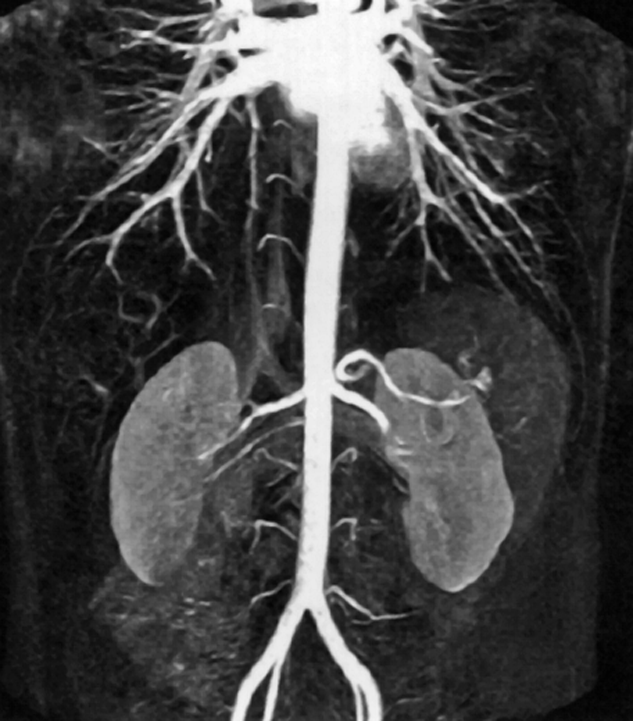

Figure 14-20:

CE-MRA of the abdominal aorta.